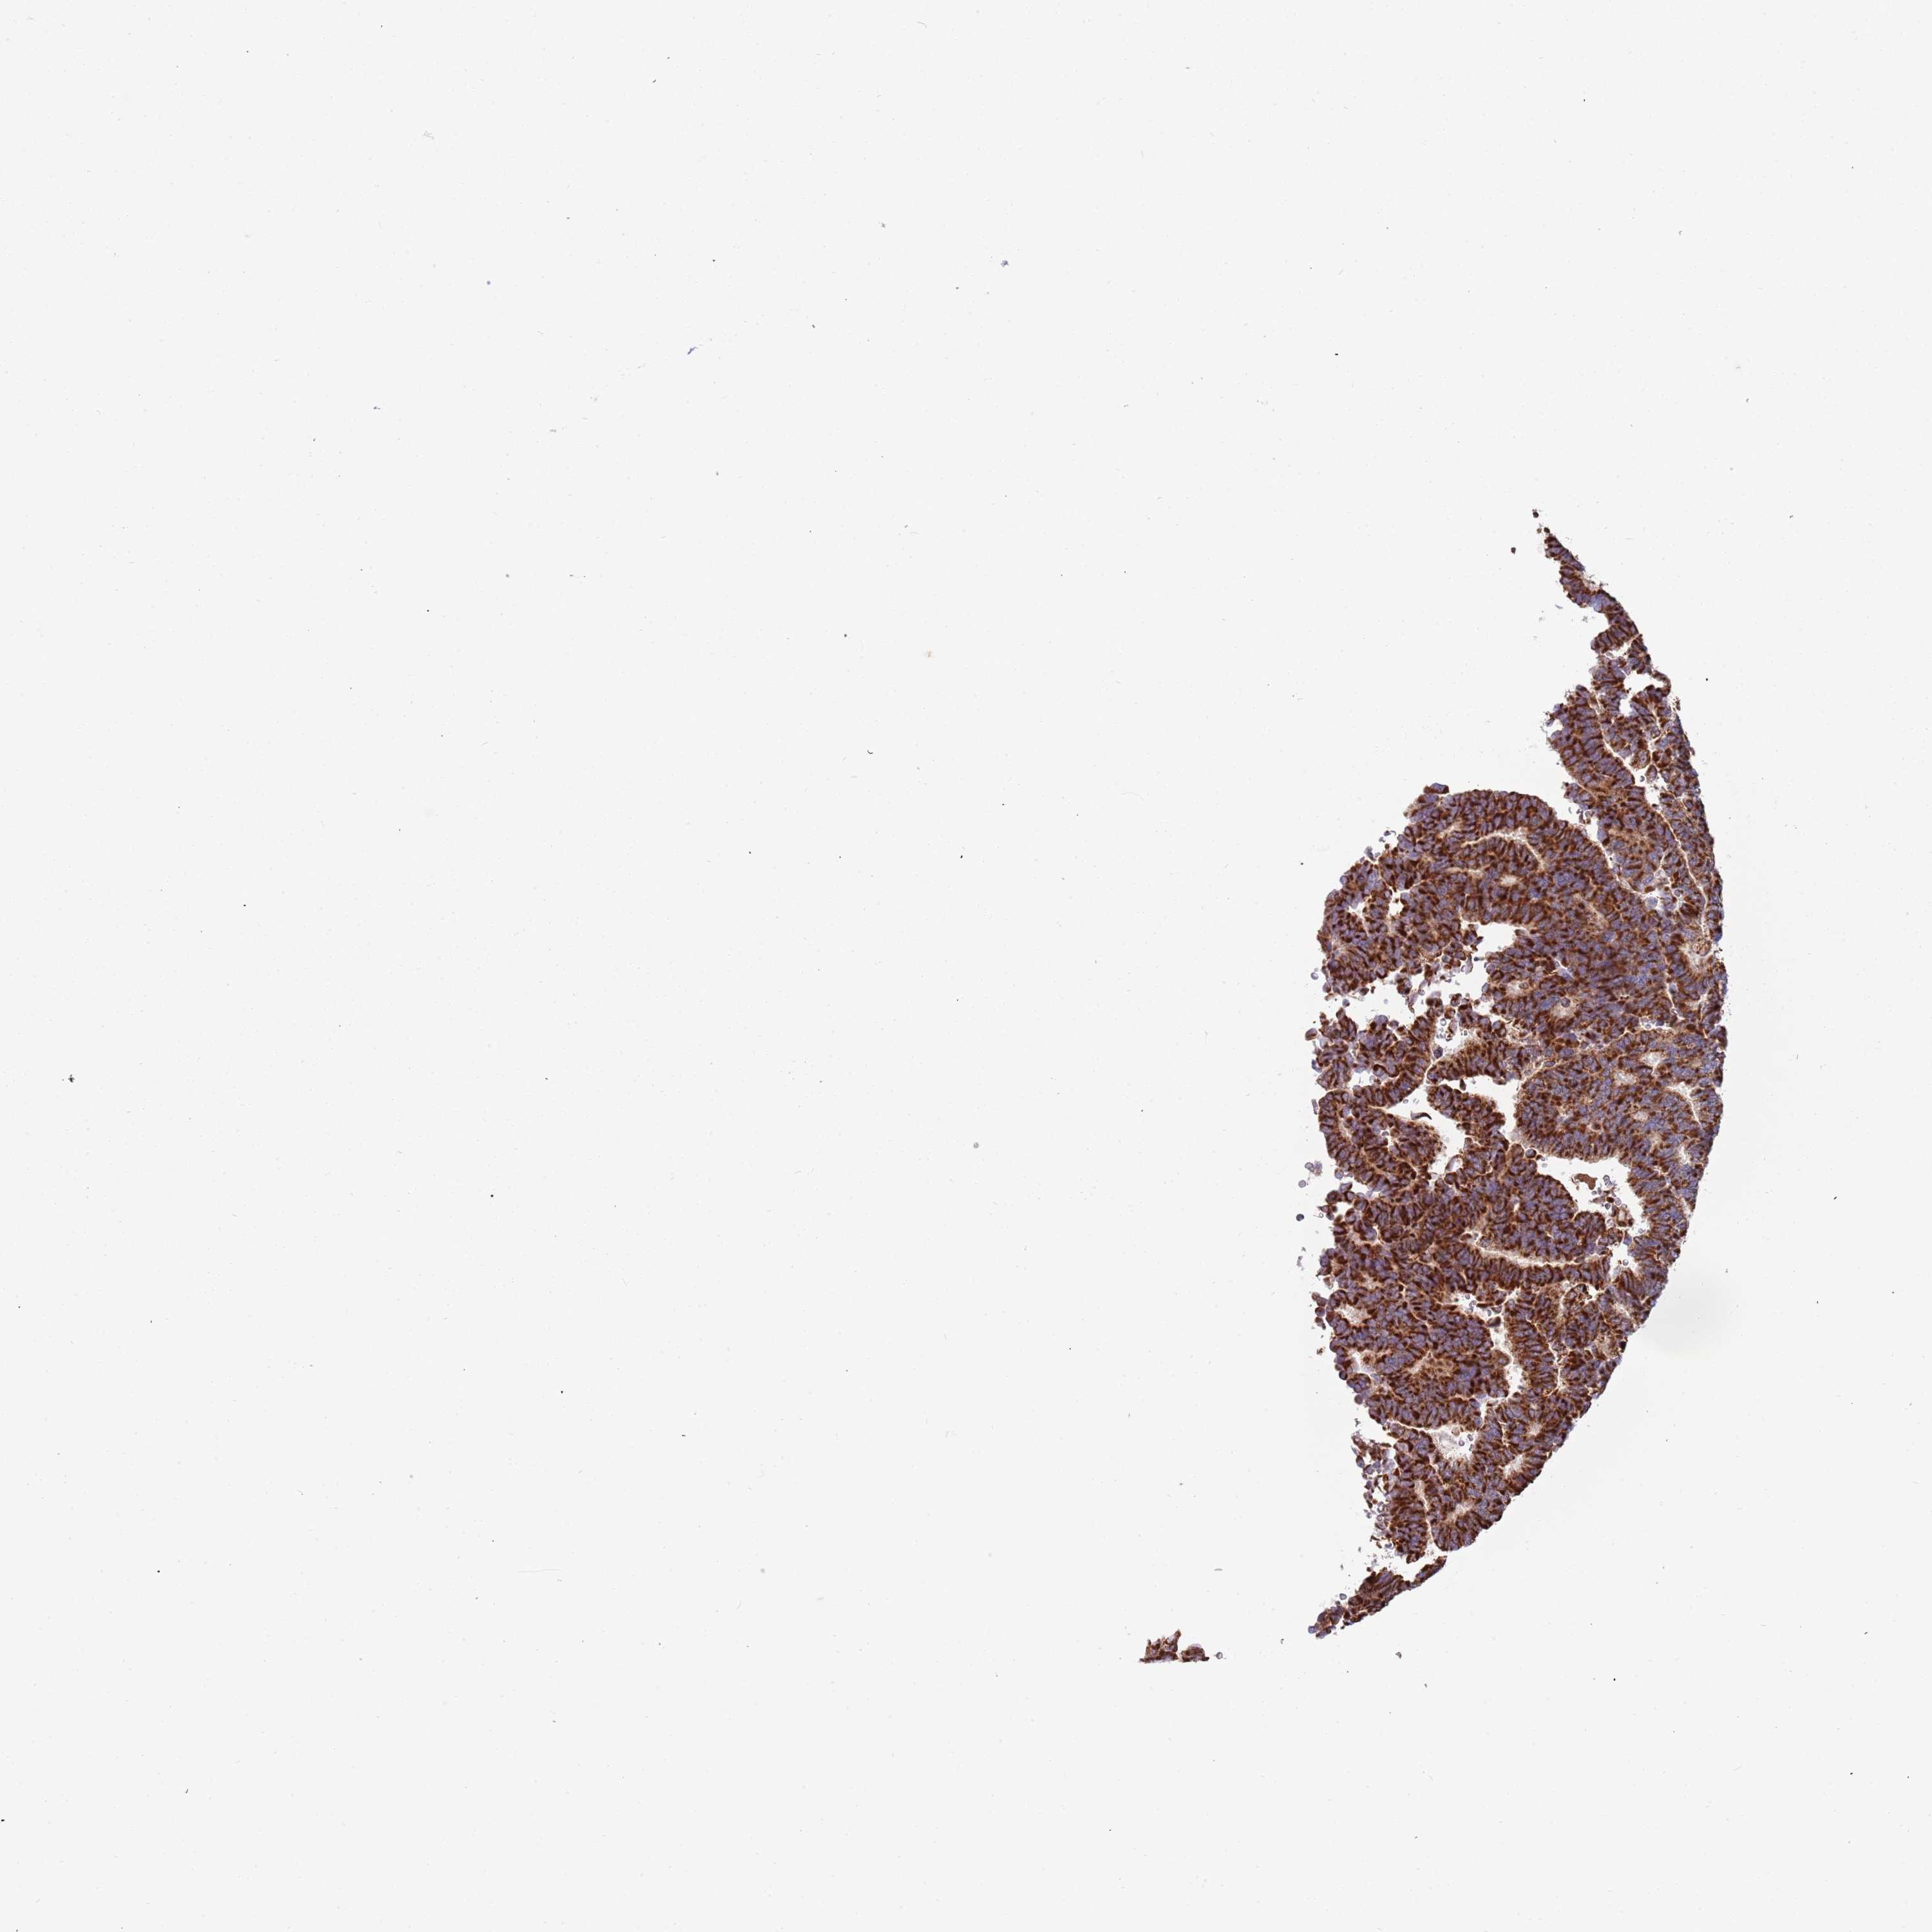

THYROID CANCER - Protein expressioni

A mouse-over function shows sample information and annotation data. Click on an image to view it in a full screen mode. Samples can be filtered based on level of antibody staining by selecting one or several of the following categories: high, medium, low and not detected. The assay and annotation is described here.

Note that samples used for immunohistochemistry by the Human Protein Atlas do not correspond to samples in the TCGA dataset.

Antibody stainingi

Antibody staining in the annotated cell types in the current human tissue is reported as not detected, low, medium, or high, based on conventional immunohistochemistry profiling in selected tissues. This score is based on the combination of the staining intensity and fraction of stained cells.

Each image is clickable and will lead to virtual microscopy that enables deeper exploration of all samples and also displays staining intensity scores, fraction scores and subcellular localization as well as patient and tissue information for each sample.

Antibody HPA043229

Antibody HPA048661

Staining

High

Medium

Low

Not detected

Intensity

Strong

Moderate

Weak

Negative

Quantity

>75%

75%-25%

<25%

None

Location

Nuclear

Cytoplasmic/membranous

Cytoplasmic/membranous,nuclear

Follicular adenoma carcinoma, NOS

Papillary adenocarcinoma, NOS